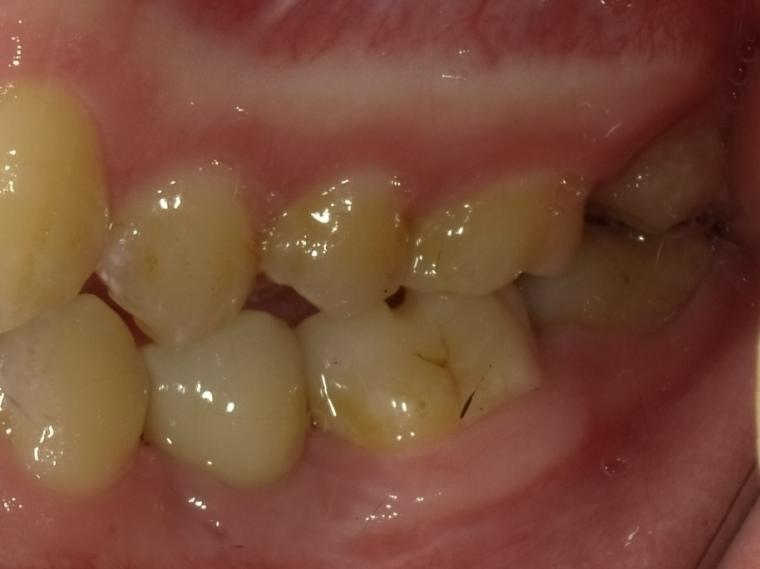

下顎小臼歯一本欠損症例(先天性欠損)

19歳女性/下1本欠損/インプラント埋込手術

下顎第二小臼歯が先天性の欠損の患者さんです。

乳歯が生えていましたが、状態が悪くなり抜歯となりました。

他の歯の健康を考えマウスピース矯正で歯列を整えてからインプラントを1本埋込しました。